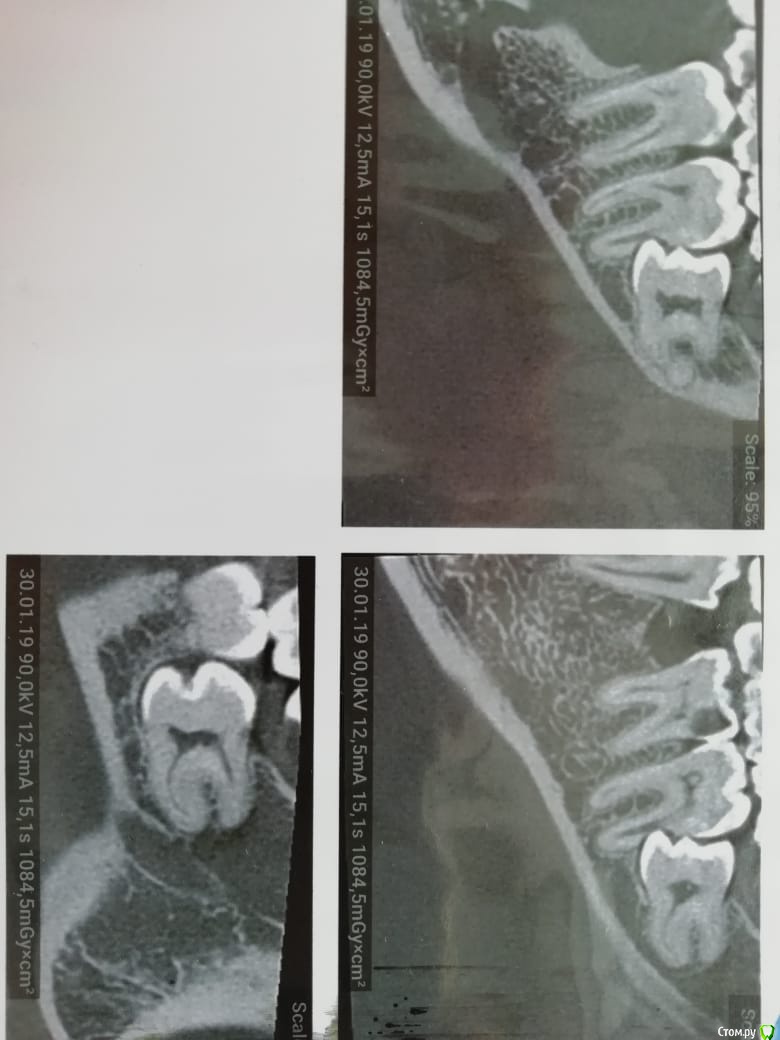

___49___ Опубликовано 30 января, 2019 Поделиться Опубликовано 30 января, 2019 (изменено) Дано на Rg: Вижу два варианта решения задачи. - могу убрать 8ку с одномоментной гемисекцией ( заранее пролеченного 7го зуба) дистального корня 7ки . Далее вкв в мезиальный корень 7ки , лечение 6ки под коронку и изготовление мостовидного протеза с опрой на 6\7 и консолью 5ка . - можно депульпировать 7ку , во время удаления 8 ки закрыть перфу прорутом . 2 вариант на мой взгляд менее прогнозируемый .... у кого какие мысли коллеги ? Изменено 30 января, 2019 пользователем ___49___ Ссылка на комментарий

___49___ Опубликовано 30 января, 2019 Автор Поделиться Опубликовано 30 января, 2019 (изменено) При предложенном Вами выше варианте дальнейшего протезирования - не факт.почему ? 6ка после пульпита будет , пломба на 1\3 или 1\2 зуба выйдет(пардон вам этого не видно наверное, виноват, добавлю срезы ) , коронки пилить будет кадкам , консоль в перед при опоре на 1.5 зуба вполне жизнеспособная конструкция , затруднения в гигиене - суперфлос в руки ( гигиена это общая проблема - либо есть либо нет) Изменено 30 января, 2019 пользователем ___49___ Ссылка на комментарий

___49___ Опубликовано 31 января, 2019 Автор Поделиться Опубликовано 31 января, 2019 (изменено) Процесс ведь там не кариозный,а вполне себе асептический,почему бы не убрать 8ку,заполнить лунку графтом,ушить герметично и понаблюдать?На счет асептического сомнения есть , попробую нарисовать .А 7 живой? Как пульпа реагирует?Если живой - убрать 8, дать зажить ране 3-4 недели, переоценить 7. Он вполне может остаться живым.7ка живая - на холодное реакция выраженная, но не продолжительная , перкуссия болезнена ( но это не из-за Pt а из-за соприкосновения с 8 кой) Ваше предложение интересное, как и выше предложенные варианты , спасибо всем за участие . Буду говорить с пациентом , о этапах и рисках всех вариантов . Изменено 31 января, 2019 пользователем ___49___ Ссылка на комментарий